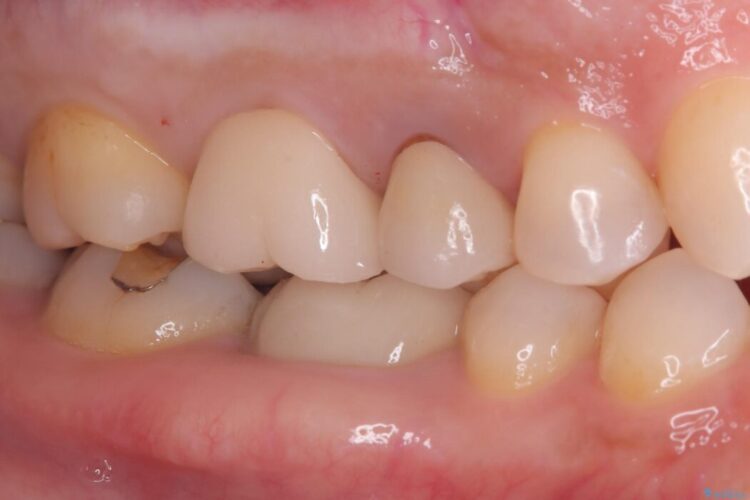

詰め物内部の虫歯治療、隠れた根管の発見

詰め物内部の虫歯治療、隠れた根管の発見 ビフォー 詰め物内部の虫歯治療、隠れた根管の発見 アフター

奥歯の詰め物が取れたとご来院された患者様です。